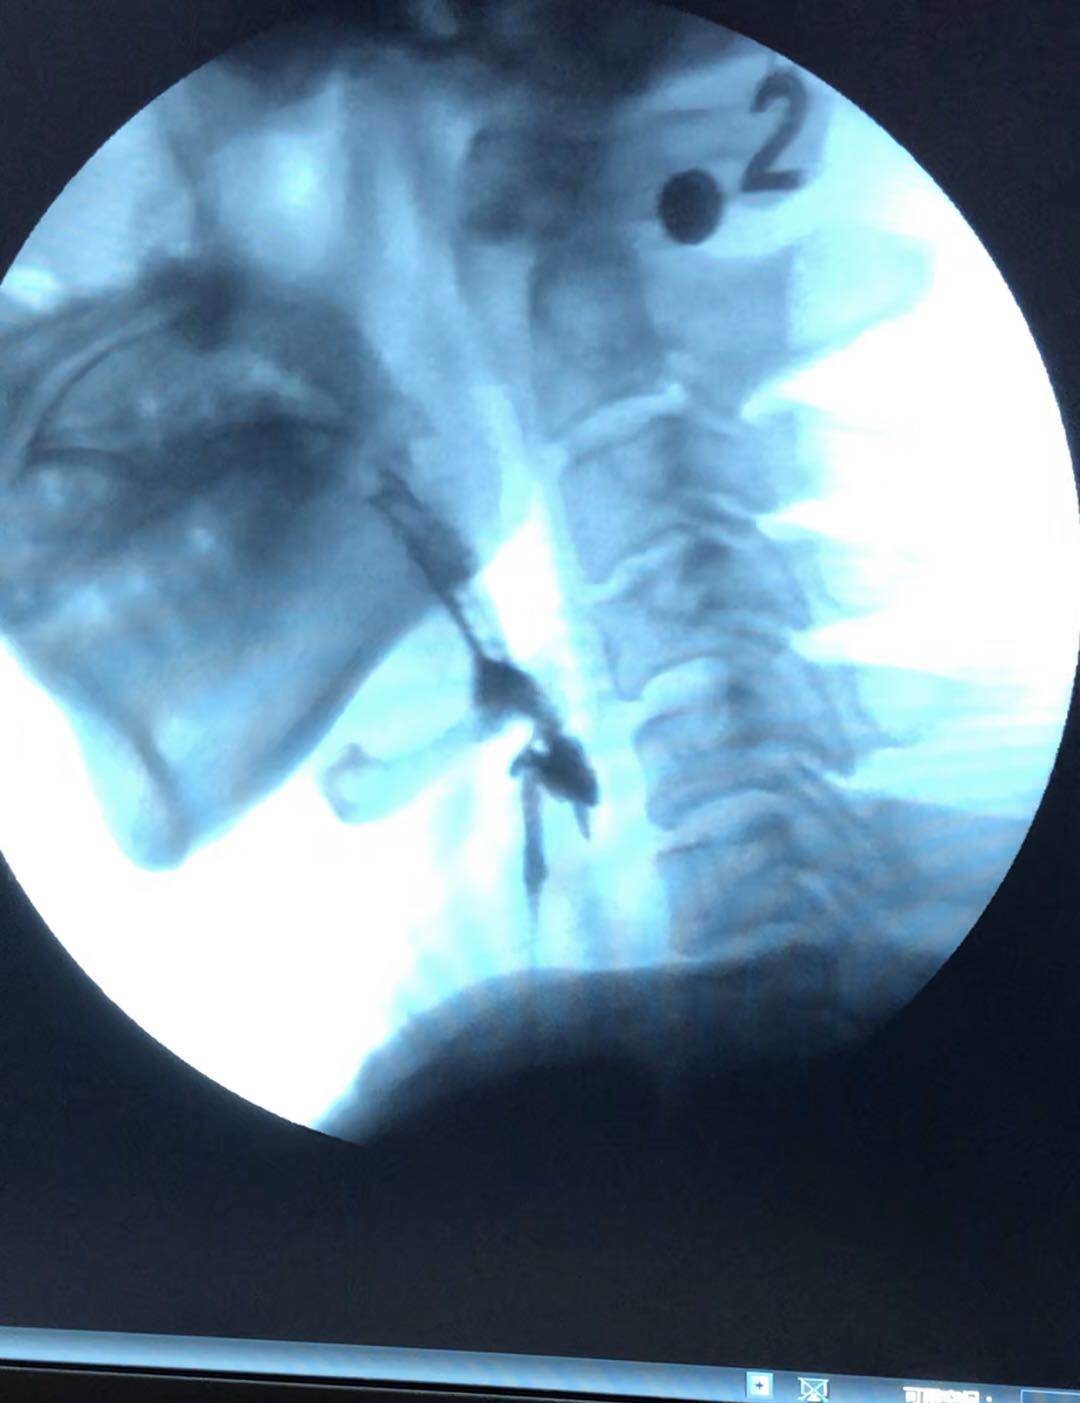

自2014年康复医学科开科以来,每年收治吞咽障碍患者200余例,在康复医师、康复治疗师、康复护士和传统的中医针灸等团队的努力下,使吞咽障碍患者疗效显著。2018年6月份以来,开展了吞咽造影检查50余例,患者经过标准化的临床评估和进一步的吞咽造影检查,使治疗师的治疗更有针对性,使患者在最短的时间得到最有效的治疗,大大提高了治愈率,使患者早日能够经口进食,享受美味。